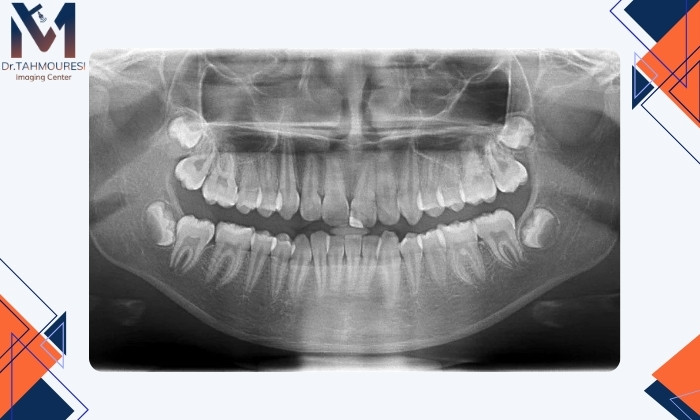

ترکهای مویی ممکن است با چشم یا حتی رادیوگرافی معمول دیده نشوند اما هنگام جویدن یا فشار دادن باعث درد ناگهانی و تیز میشوند.دندانقروچه (براکسیسم)